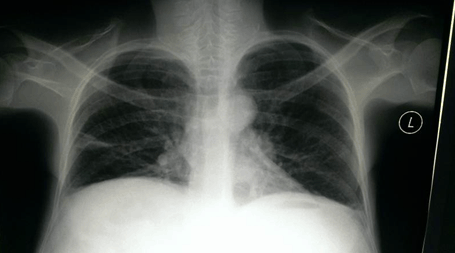

A 48-year-old perimenopausal woman came with history of abdominal distension since last 8–10 years, difficulty in breathing with increasing intensity over the past few months. She became very uncomfortable in supine position. She had no medical or surgical history of note. She is para 3 with uneventful vaginal deliveries. She took no regular medication and had no family medical history of note (Figure 1). Auscultation revealed absence of breath sounds at the right lower hemithorax and normal heart sounds. On abdominal examination massive ascites was noted. The mass was not palpable because of the tense ascites. Chest X-ray revealed mild right sided pleural effusion (Figure 2). Electrocardiography was within normal limits. On ultrasound of abdomen, a massive multi septate cystic mass with suspected ovarian origin, with massive ascites was noted. Computed tomography scan revealed a huge multiseptate mass with solid and cystic components measuring 42x31 cm arising from the pelvis. Left side ovary was not visualized and uterus was normal sized. Massive ascites was noted. No obvious lymphadenopathy was seen. Her serum CA 125 was 49 U/ml (normal <35U/ml). AFP was within normal limits while b-hCG was not detectable. Her serum proteins were slightly below normal. Routine blood investigations, including LFT’s and RFT’s were within normal limits. Ascitic tap fluid cytology revealed low cellular fluid comprising of lymphocytes and mesothelial cells. No evidence of malignancy was noted.

Figure 2: Preoperative chest X-ray of patient.